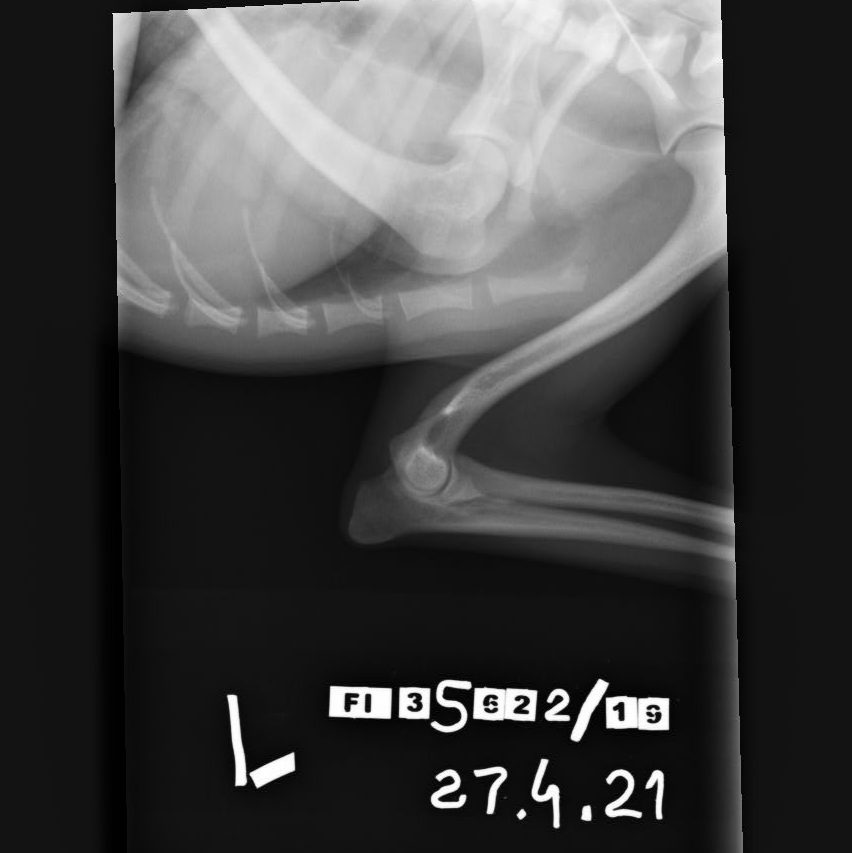

Kyynärnivelen kasvuhäiriö

Elbow dysplasia, ED

Kyynärnivelen kasvuhäiriön periytymiseen vaikuttaa useita eri geenejä. Kyynärnivelen kasvuhäiriö on yleisempää uroksilla todennäköisesti urosten suuremman painon ja mahdollisesti myös hormonaalisten tekijöiden takia. Nykykäsityksen mukaan perinnöllisillä tekijöillä on suurin osuus kyynärnivelen kasvuhäiriön synnyssä, mutta ympäristötekijöillä on osuutensa sen ilmenemisessä.

Kaikissa kyynärnivelen kasvuhäiriöissä oireet alkavat keskimäärin 4 – 7 kuukauden iässä. Tyypillinen oire on ontuminen, joka voi pahentua rasituksessa tai olla voimakkainta levon jälkeen. Ontuminen voi olla jatkuvaa tai ajoittaista. Omistajan voi olla vaikea havaita koiran ontumista, jos kasvuhäiriö on molemminpuolinen. Toisinaan kasvuhäiriö on molemmissa kyynärnivelissä, vaikka koira ontuu vain toista jalkaa. Usein oireet huomataan vasta aikuisiällä ja silloin oireet johtuvat kasvuhäiriön seurauksena kehittyneestä nivelrikosta. Kiinnittymätön kyynärpään uloke ei välttämättä oireile nuorella koiralla ja se voi olla röntgenkuvauksen sivulöydös.